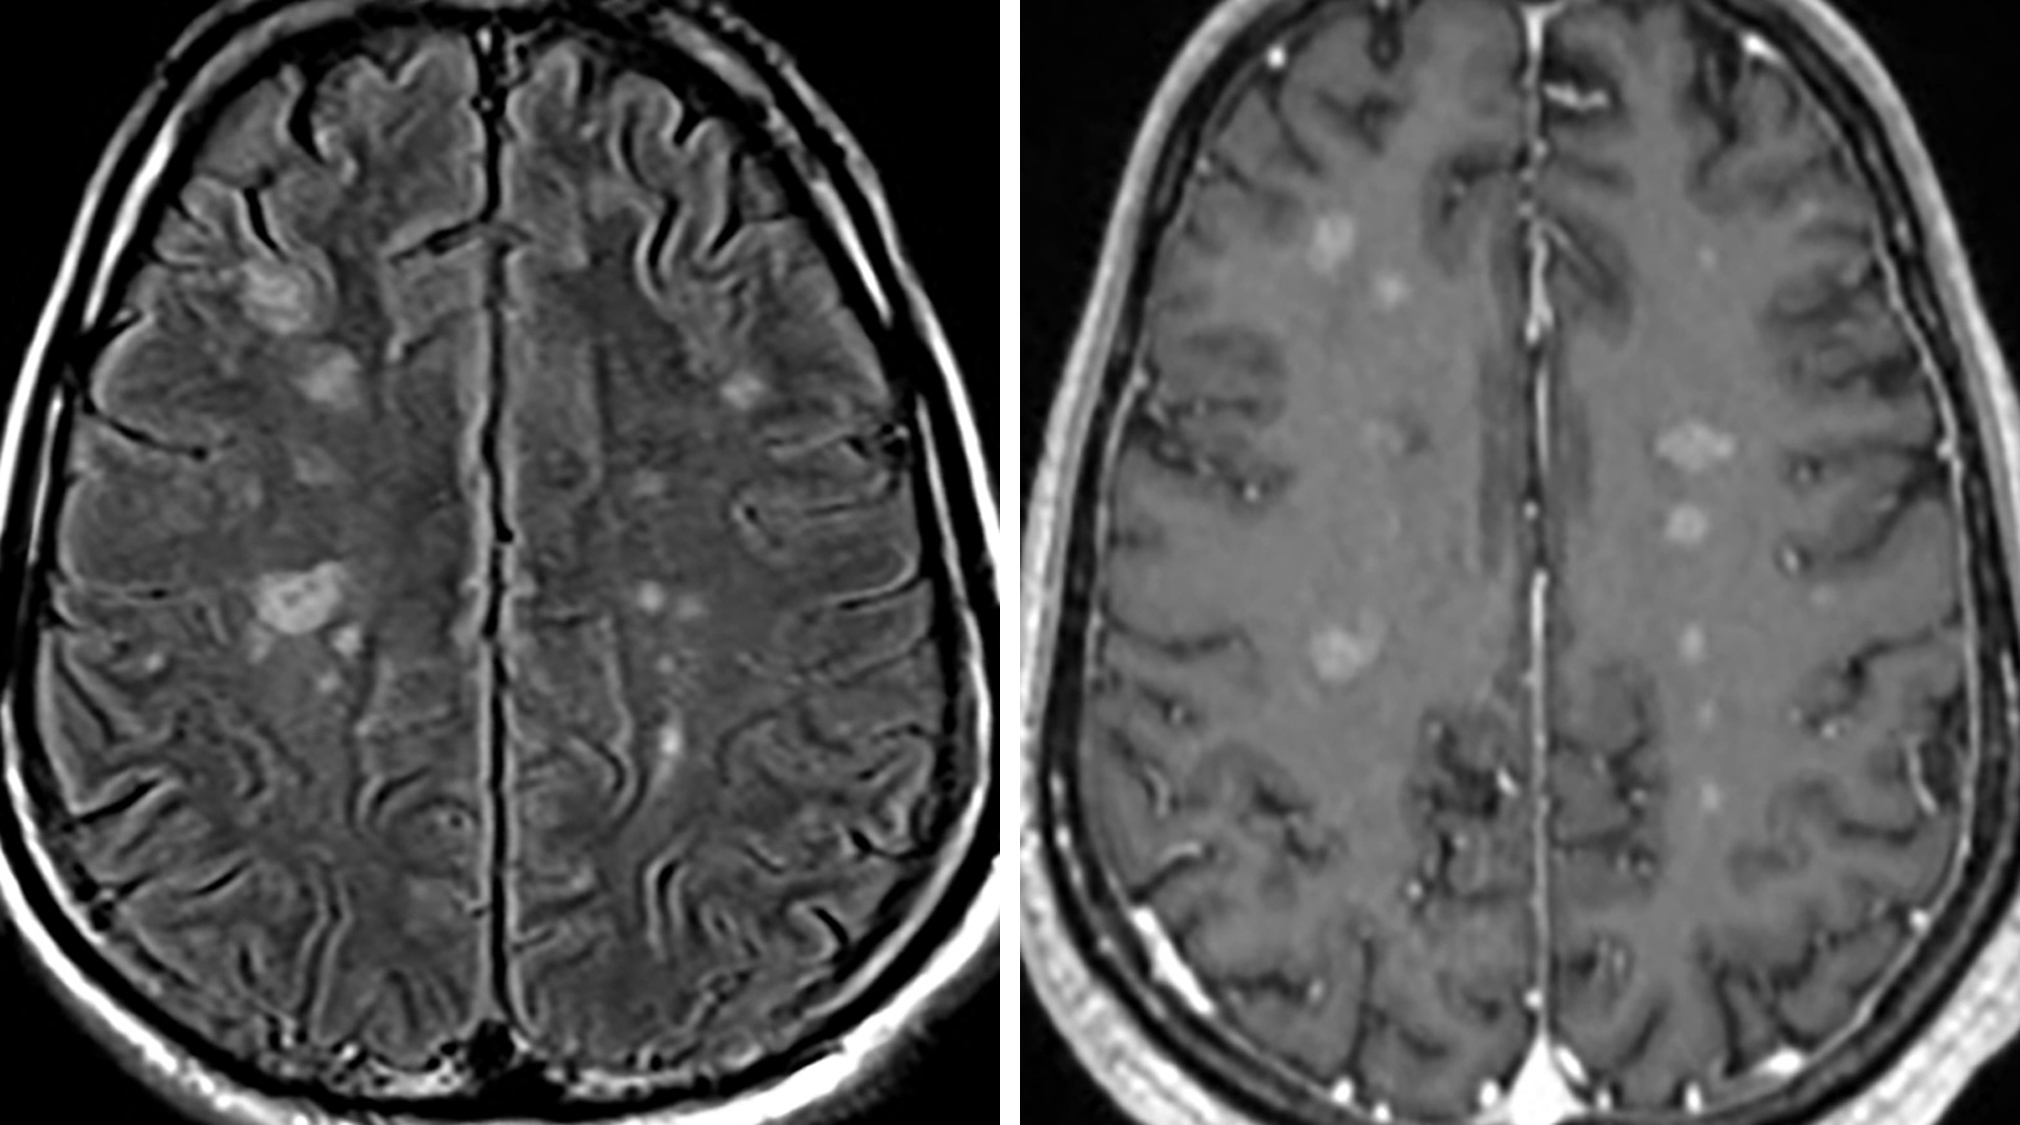

MRI of brain showing plaques of multiple sclerosis Stock Photo Alamy Plaques In Brain And Spine brain lesions are areas of brain tissue that show damage from injury or disease. Demyelinating disorders of the central nervous system (cns) that affect the brain and spine have. When lesions develop on your brain or spinal cord, they can disrupt the movement of signals along your nerves. the pathologic hallmark of multiple sclerosis (ms) is multiple focal. Plaques In Brain And Spine.

Imaging in multiple sclerosis Journal of Neurology, Neurosurgery Plaques In Brain And Spine the pathologic hallmark of multiple sclerosis (ms) is multiple focal areas of myelin loss within the cns called plaques or lesions. a lesion is an area of damage in the brain or spinal cord. brain lesions are areas of brain tissue that show damage from injury or disease. this damage leaves behind scar tissue that forms. Plaques In Brain And Spine.